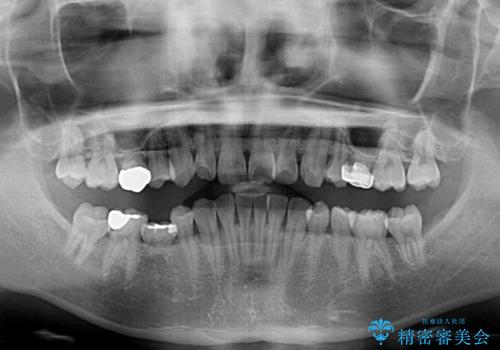

インビザラインによる矯正治療と奥歯のインプラント治療

- 咬み合わせと前歯のデコボコを気にして来院された患者様です。

前から5番目の永久歯が3本欠損しており、乳歯が残存している状態でしたが、インビザラインでも十分に対応可能と判断し、インビザラインにて矯正治療を行うこととしました。

右下の残存している乳歯は萌出しきれておらず、全く咬み合っていない状態であり、インビザラインにて移動できない可能性があるため、ワイヤー矯正の併用も念頭に置いて治療を開始しました。

今回は部分的にワイヤー矯正を用いましたが、右下の乳歯は全く動かなかったため、抜歯をした上でインプラントを埋入し、オールセラミッククラウンにて補綴治療を行いました。